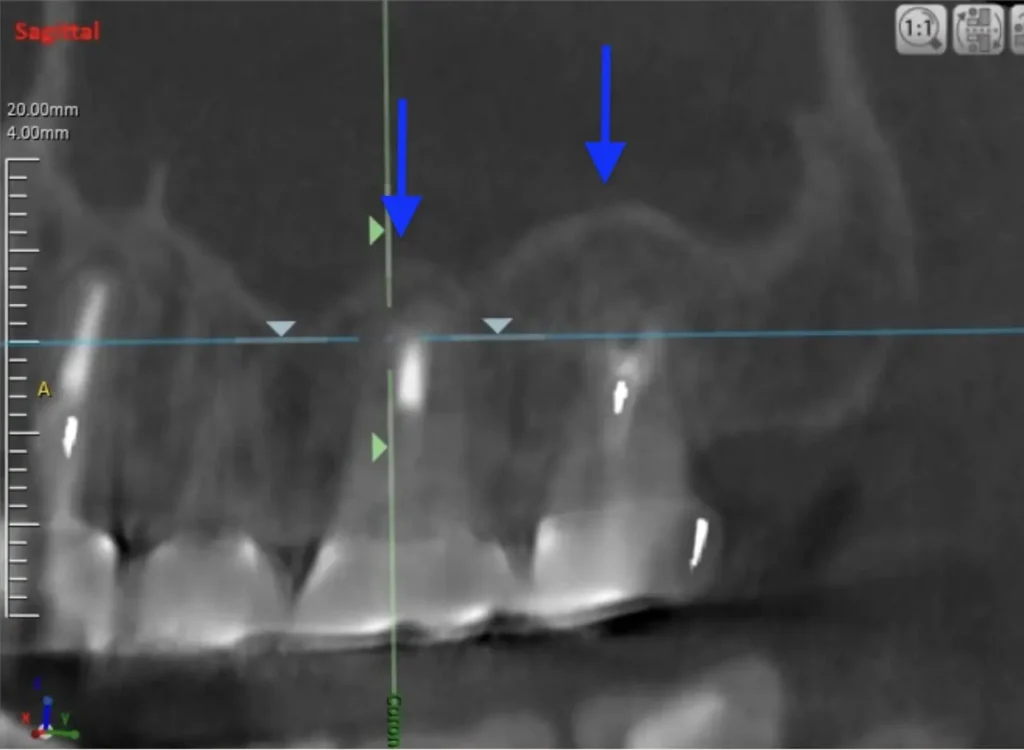

CT画像

副鼻腔の骨の壁を突き破っています

術後3年CT画像

骨の穴は完全に消えました